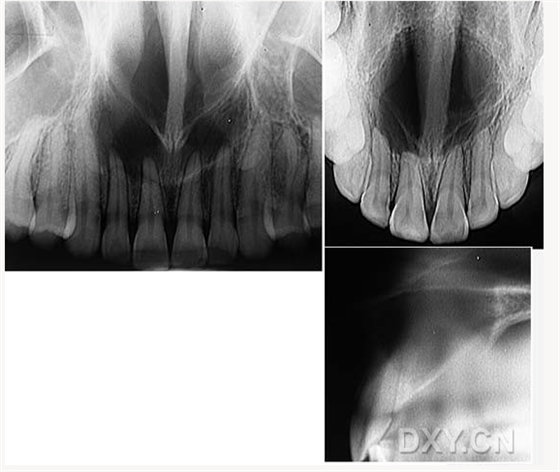

根尖囊腫

骨肉瘤

涎石病